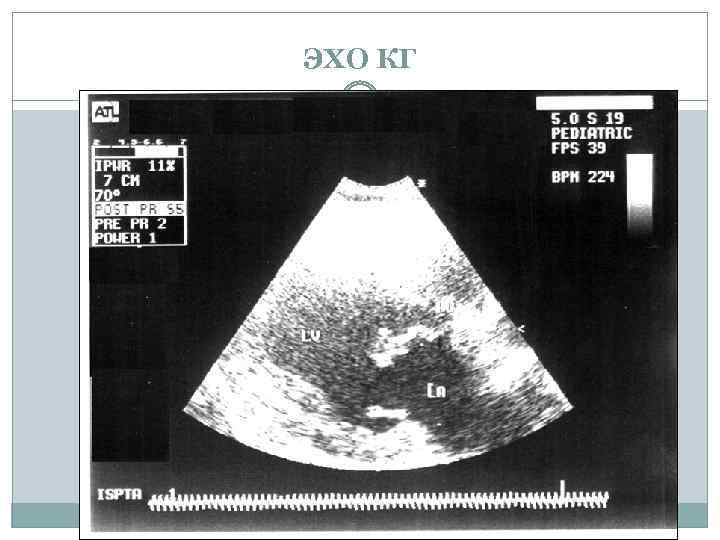

ЭХО КГ

ЭХО КГ